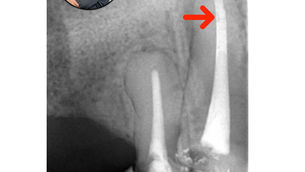

Diagnóstico Endodôntico

O diagnóstico preciso é o primeiro passo do sucesso endodôntico. Conheça protocolos, testes e interpretações clínicas baseadas em evidência